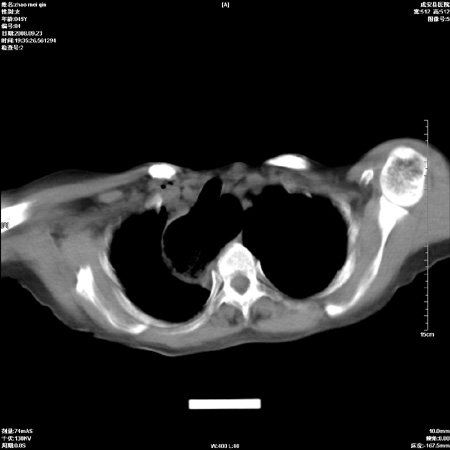

标题: CT15861:女 60 外伤后1小时 胸疼 [打印本页]

标题: CT15861:女 60 外伤后1小时 胸疼

外伤后1小时 胸疼 是外伤后引起的吗?

食道扩张明显下端逐渐变窄,倒像贲门失迟缓

食道扩张明显下端逐渐变窄,大量食物存留,象贲门失迟缓症。

非外伤性改变,典型的贲门失迟缓症